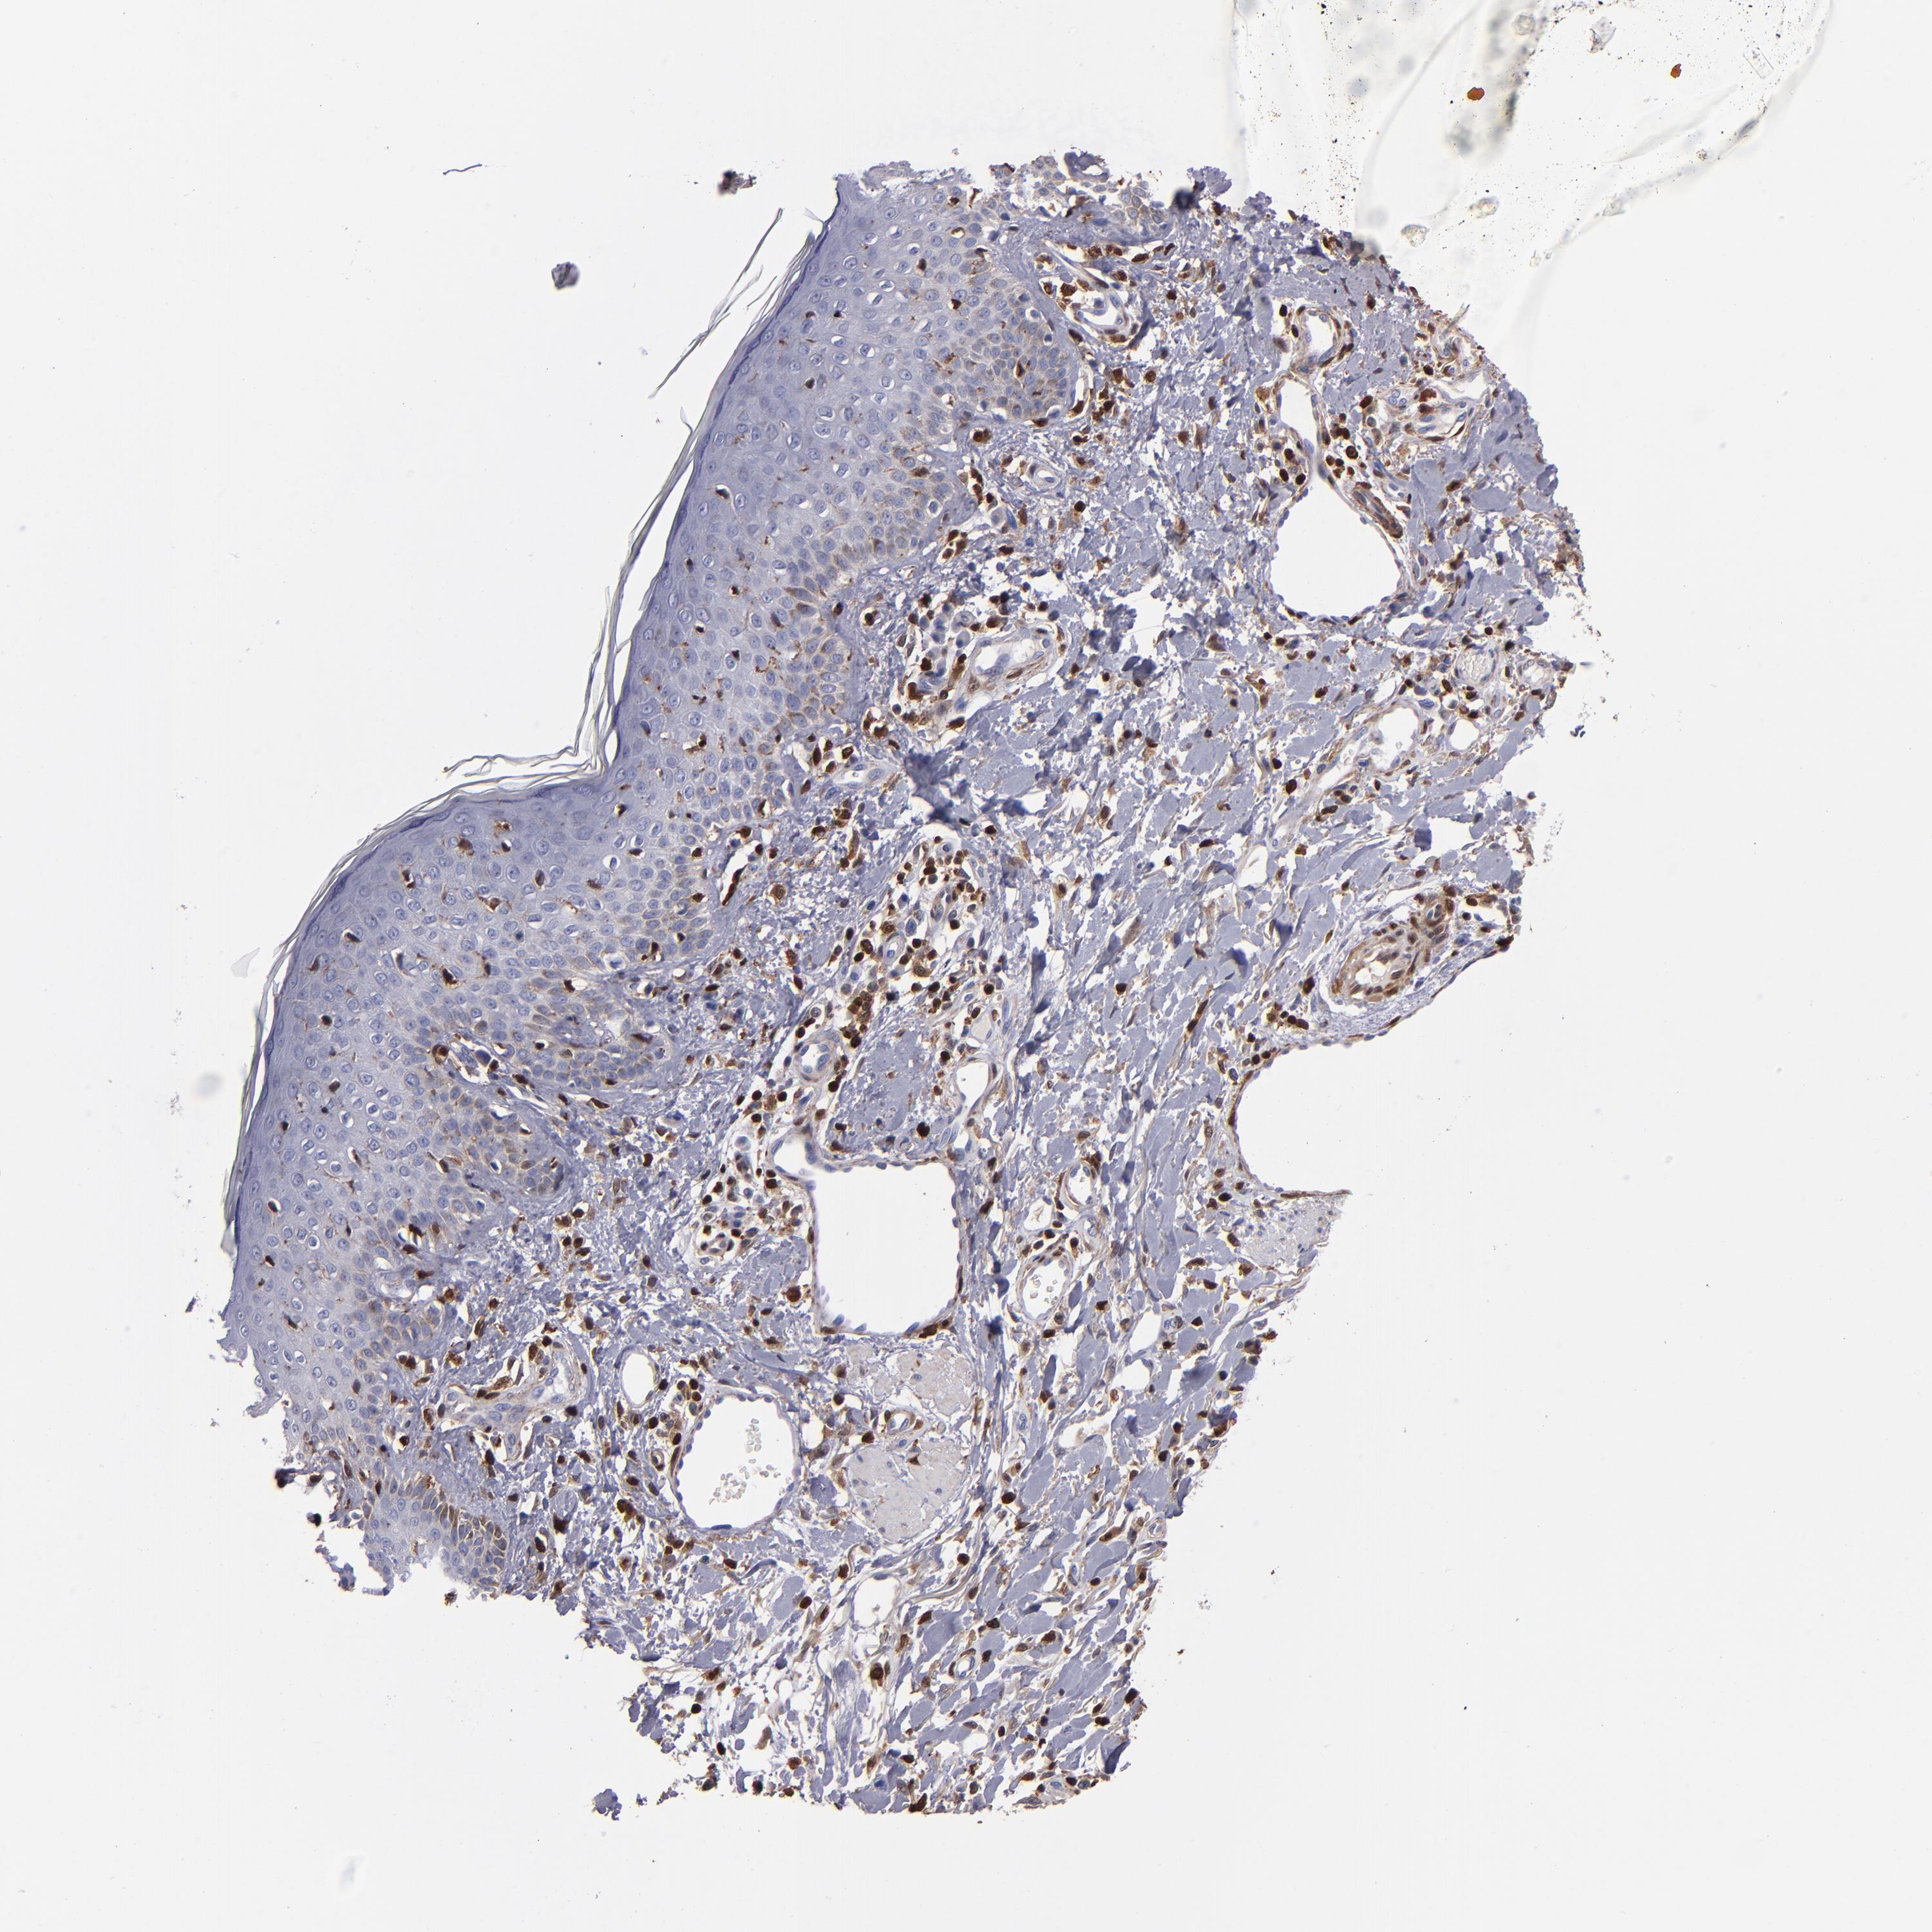

CANCER SKIN CANCER Show tissue menu

Basal cell and squamous cell cancer

SKIN CANCER - Protein expressioni

A mouse-over function shows sample information and annotation data. Click on an image to view it in a full screen mode. Samples can be filtered based on level of antibody staining by selecting one or several of the following categories: high, medium, low and not detected. The assay and annotation is described here.

Each image is clickable and will lead to virtual microscopy that enables deeper exploration of all samples and also displays staining intensity scores, fraction scores and subcellular localization as well as patient and tissue information for each sample.

HPA007973

CAB002618

CAB027387

CAB058698

CAB068227

CAB068228

Basal cell carcinoma

Squamous cell carcinoma, NOS

Squamous cell carcinoma, metastatic, NOS